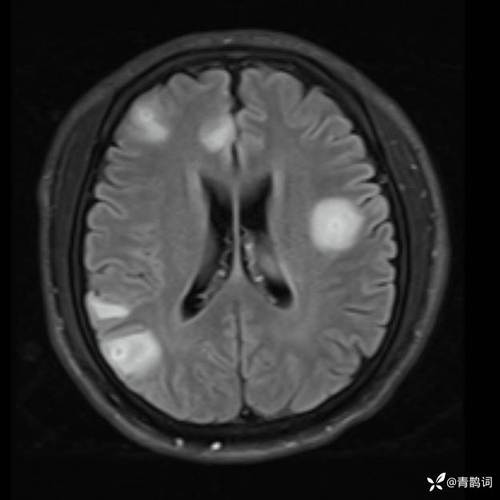

“脑梗病灶可见弥散受限”是急性脑梗死(中风)在磁共振成像(MRI)上一个非常特异和早期的“指纹”或“标志”。 它意味着脑组织由于缺血缺氧,细胞正在发生不可逆的死亡,医生可以据此在发病的早期就明确诊断脑梗。

- “弥散受限”的含义:在MRI的“弥散加权成像”(DWI)序列上,如果水分子运动受限,无法自由移动,这个区域在图像上就会显示为高信号(亮白色),这就是“弥散受限”的影像表现。

- 急性期(<1周):病灶在DWI上呈高信号(亮),而在另一个序列“表观弥散系数”(ADC)图上呈低信号(暗),这个“亮-暗”组合是急性梗死的典型表现。